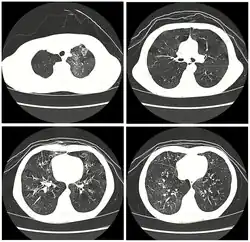

High resolution CT scan showing bronchiolitis obliterans with mosaic attenuation, bronchiectasis, air trapping and bronchial thickening[3]

Early in the disease chest radiography is typically normal but may show hyperinflation.[6] As the disease progresses a reticular pattern with thickening of airway walls may be present.[4][6] HRCT can also show air trapping when the person being scanned breathes out completely; it can also show thickening in the airway and haziness in the lungs.[11] A common finding on HRCT is patchy areas of decreased lung density, signifying reduced vascular caliber and air trapping. This pattern is often described as a "mosaic pattern", and may indicate bronchiolitis obliterans.[6]